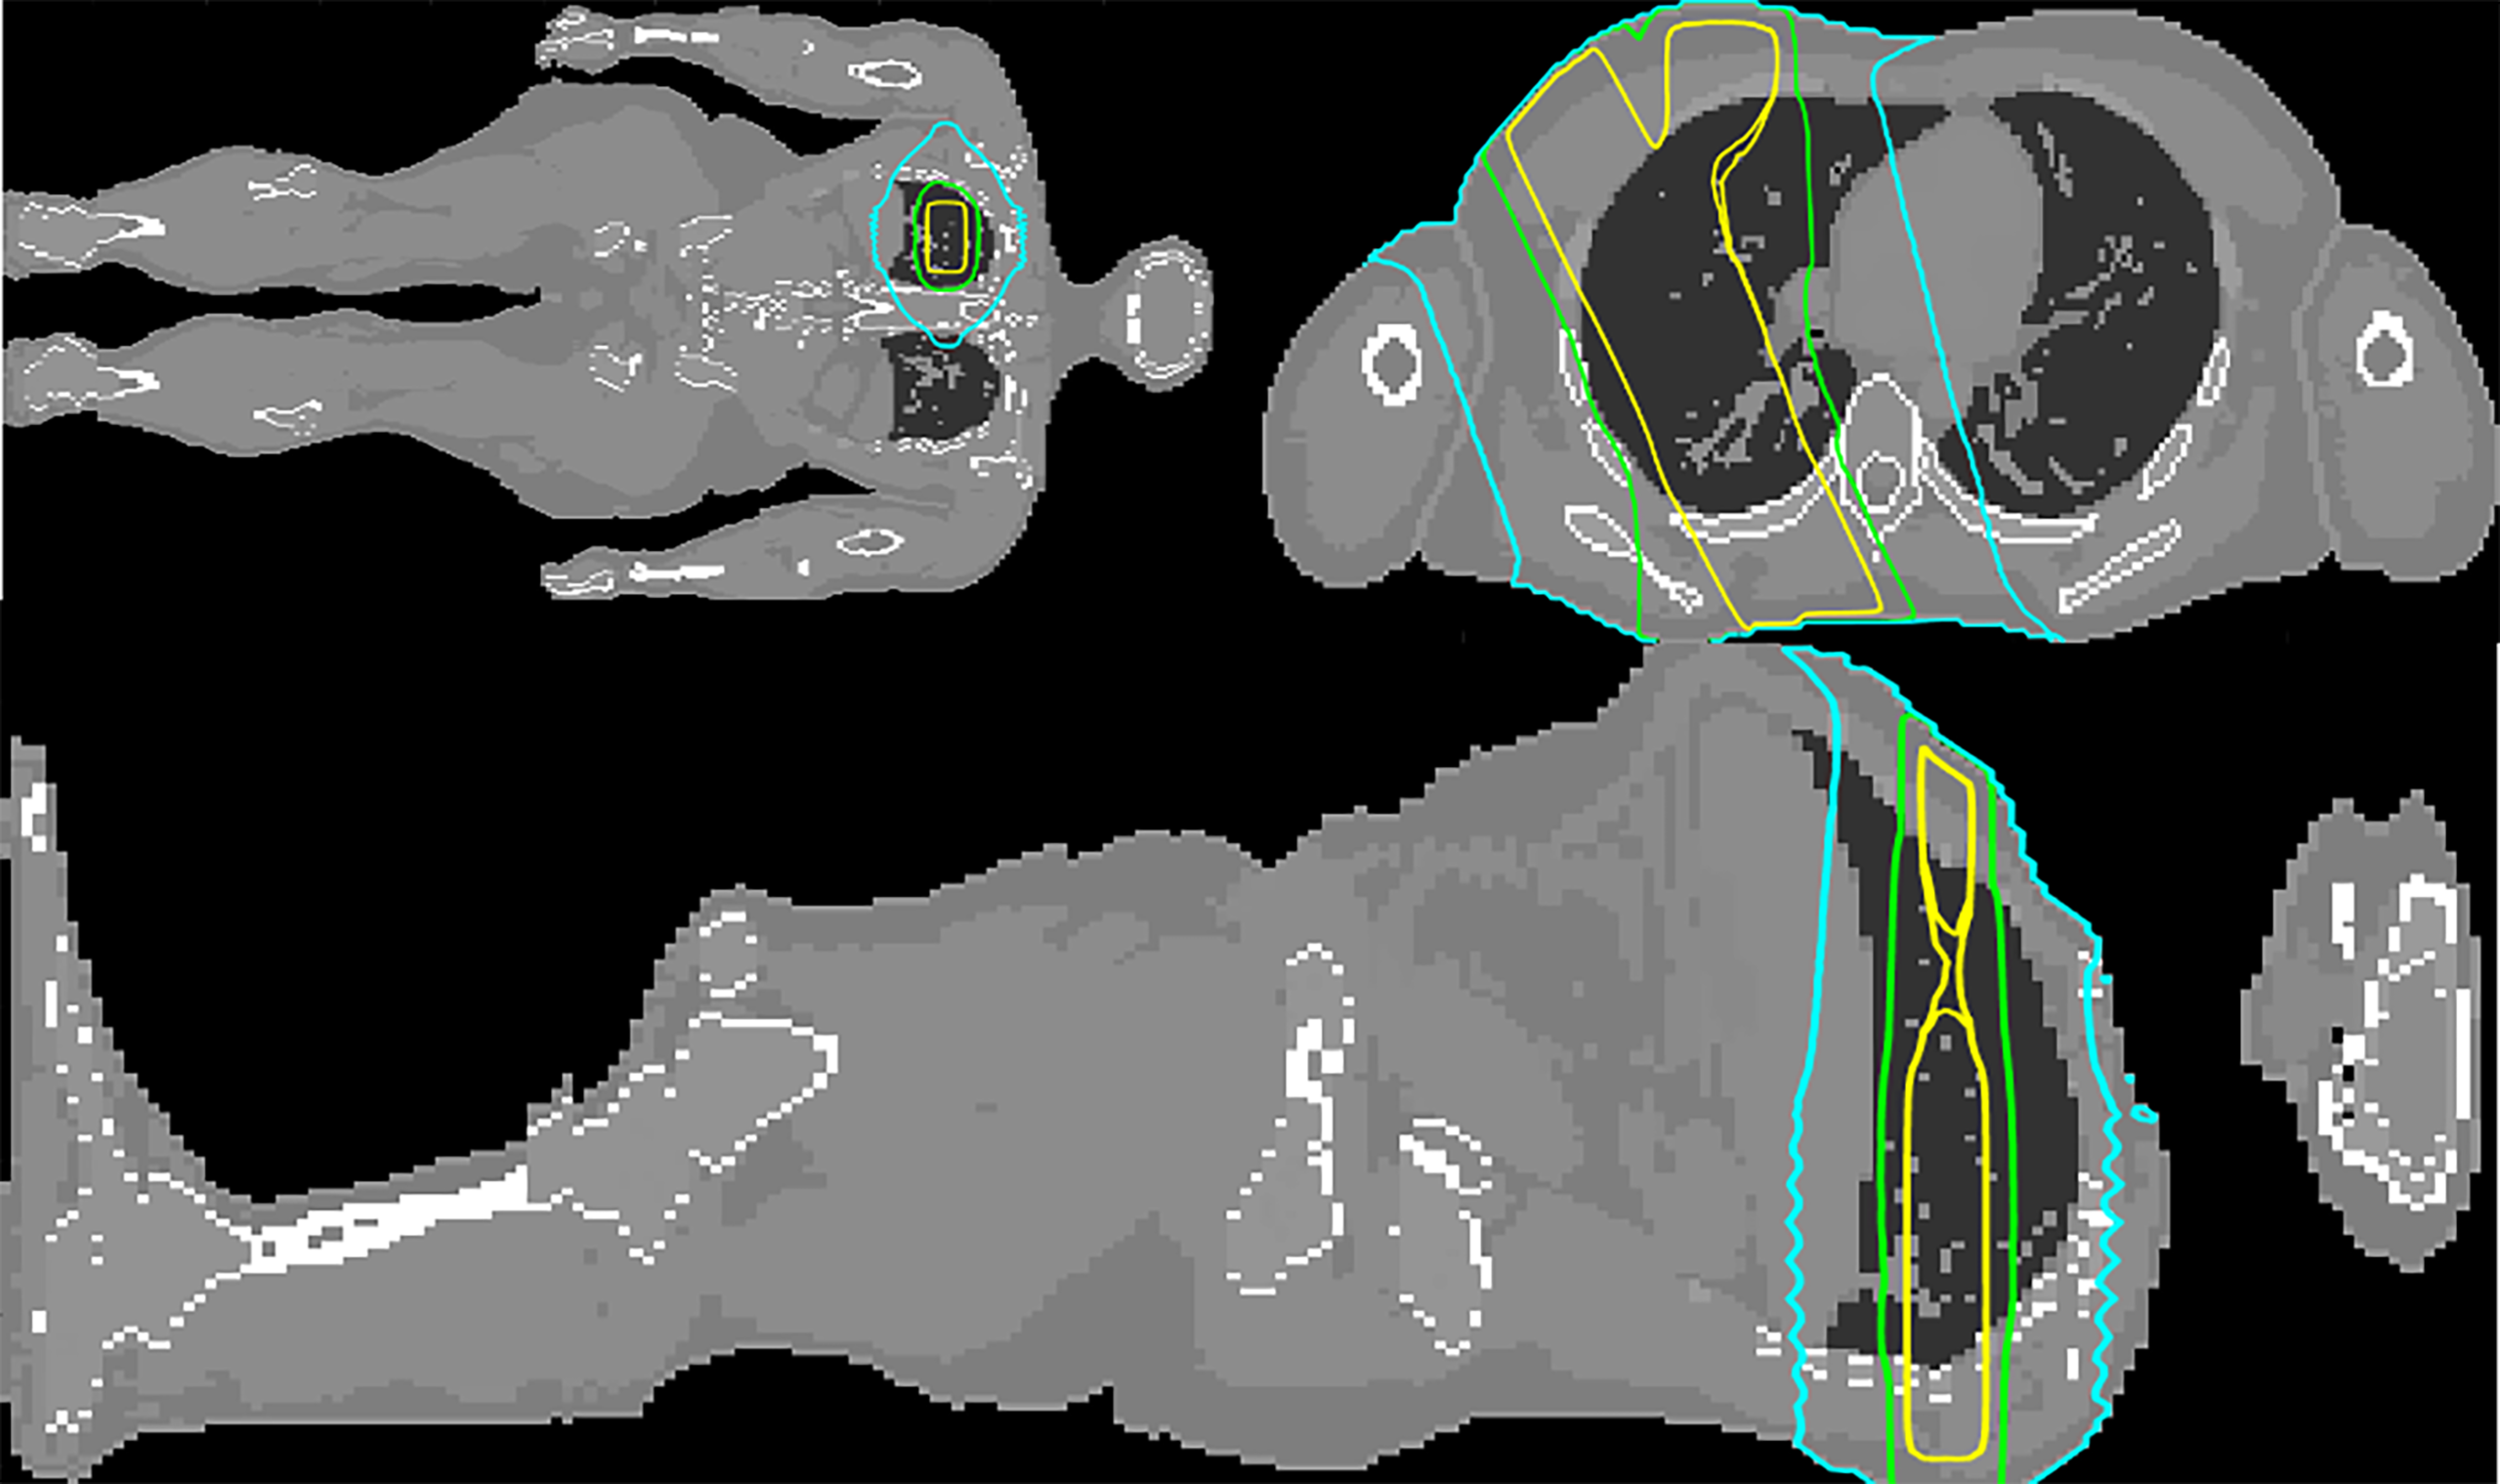

Representative isodoses calculated with MC on the ICRP 110 phantom, corresponding to the lung plan described in Testing the model using a Monte Carlo simulation of a lung treatment on the ICRP phantom, are shown in Figure 5. Figure 6 depicts the peripheral dose, relative to the isocentric dose, calculated by Periphocal 3D and MC for the same case.

Figure 5

Coronal, transversal and sagittal views at the level of the isocenter of the MC simulated upper right lung irradiation with three square beams of . The 50%, 5%, and 1% isodoses are depicted in yellow, green, and cyan, respectively.

Although Periphocal 3D represents an improvement compared to its previous version, there are some limitations to take into account. Regarding geometry and X-ray attenuation, it is worth noting that Periphocal 3D was calibrated with a nearly symmetrical eight-field treatment (see Figure 2) and Equation 1 has spherical symmetry. Thus, the model should become less accurate when non-symmetrical isodoses, usually associated with plans with fewer beams, as in Figure 5 (lung case), are generated. Luckily, VMAT and IMRT treatments usually consider several beam entries around the isocenter. Another possible issue is the attenuation of X-rays inside the patients when significant tissue heterogeneities are present. Since Periphocal 3D was calibrated in the abdomen, which is mainly composed of soft tissue, its application to the treatments of tumors in tissues with different X-ray attenuation characteristics will necessarily imply worse accuracy. This can be observed in Figure 6, where calculations within the soft tissue after the lung shows an overestimation of the dose because it does not take into consideration the smaller backscatter contribution from the lung tissue. Additionally, in bone, as Periphocal 3D assumes that everything is water, the calculated absorbed dose underestimates the MC calculation.